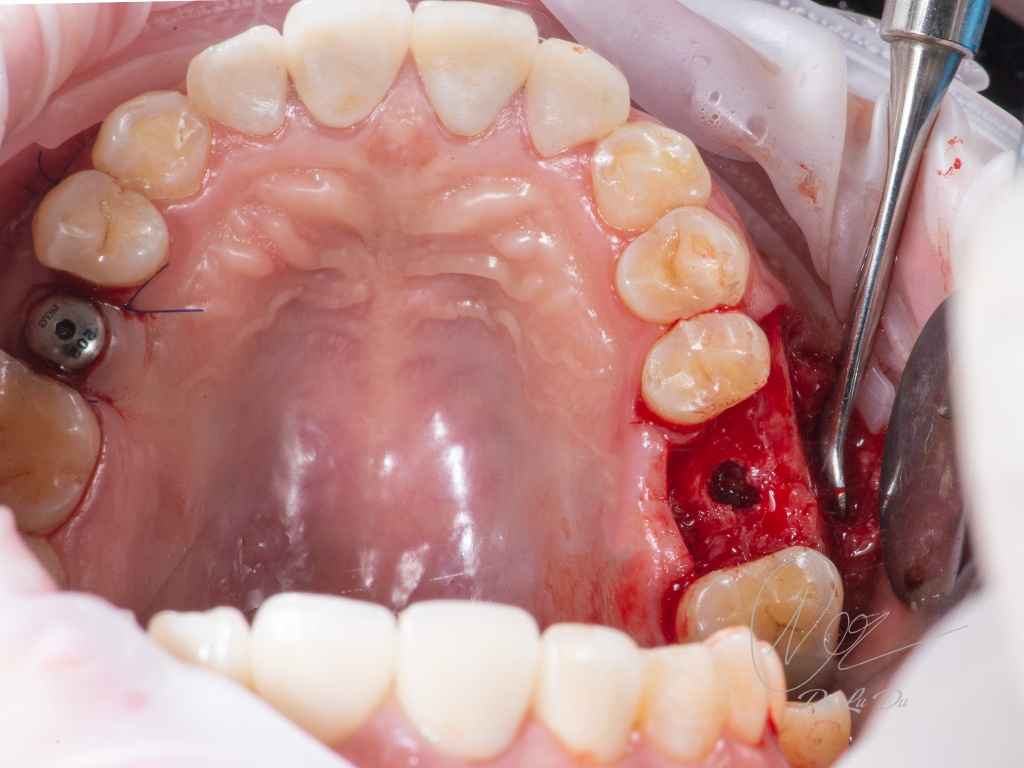

Имплантация AnyRidge с двусторонним закрытым синус-лифтингом.

Осложнения: правосторонний гайморит.

Кейс MINEC: Dr Lu Du